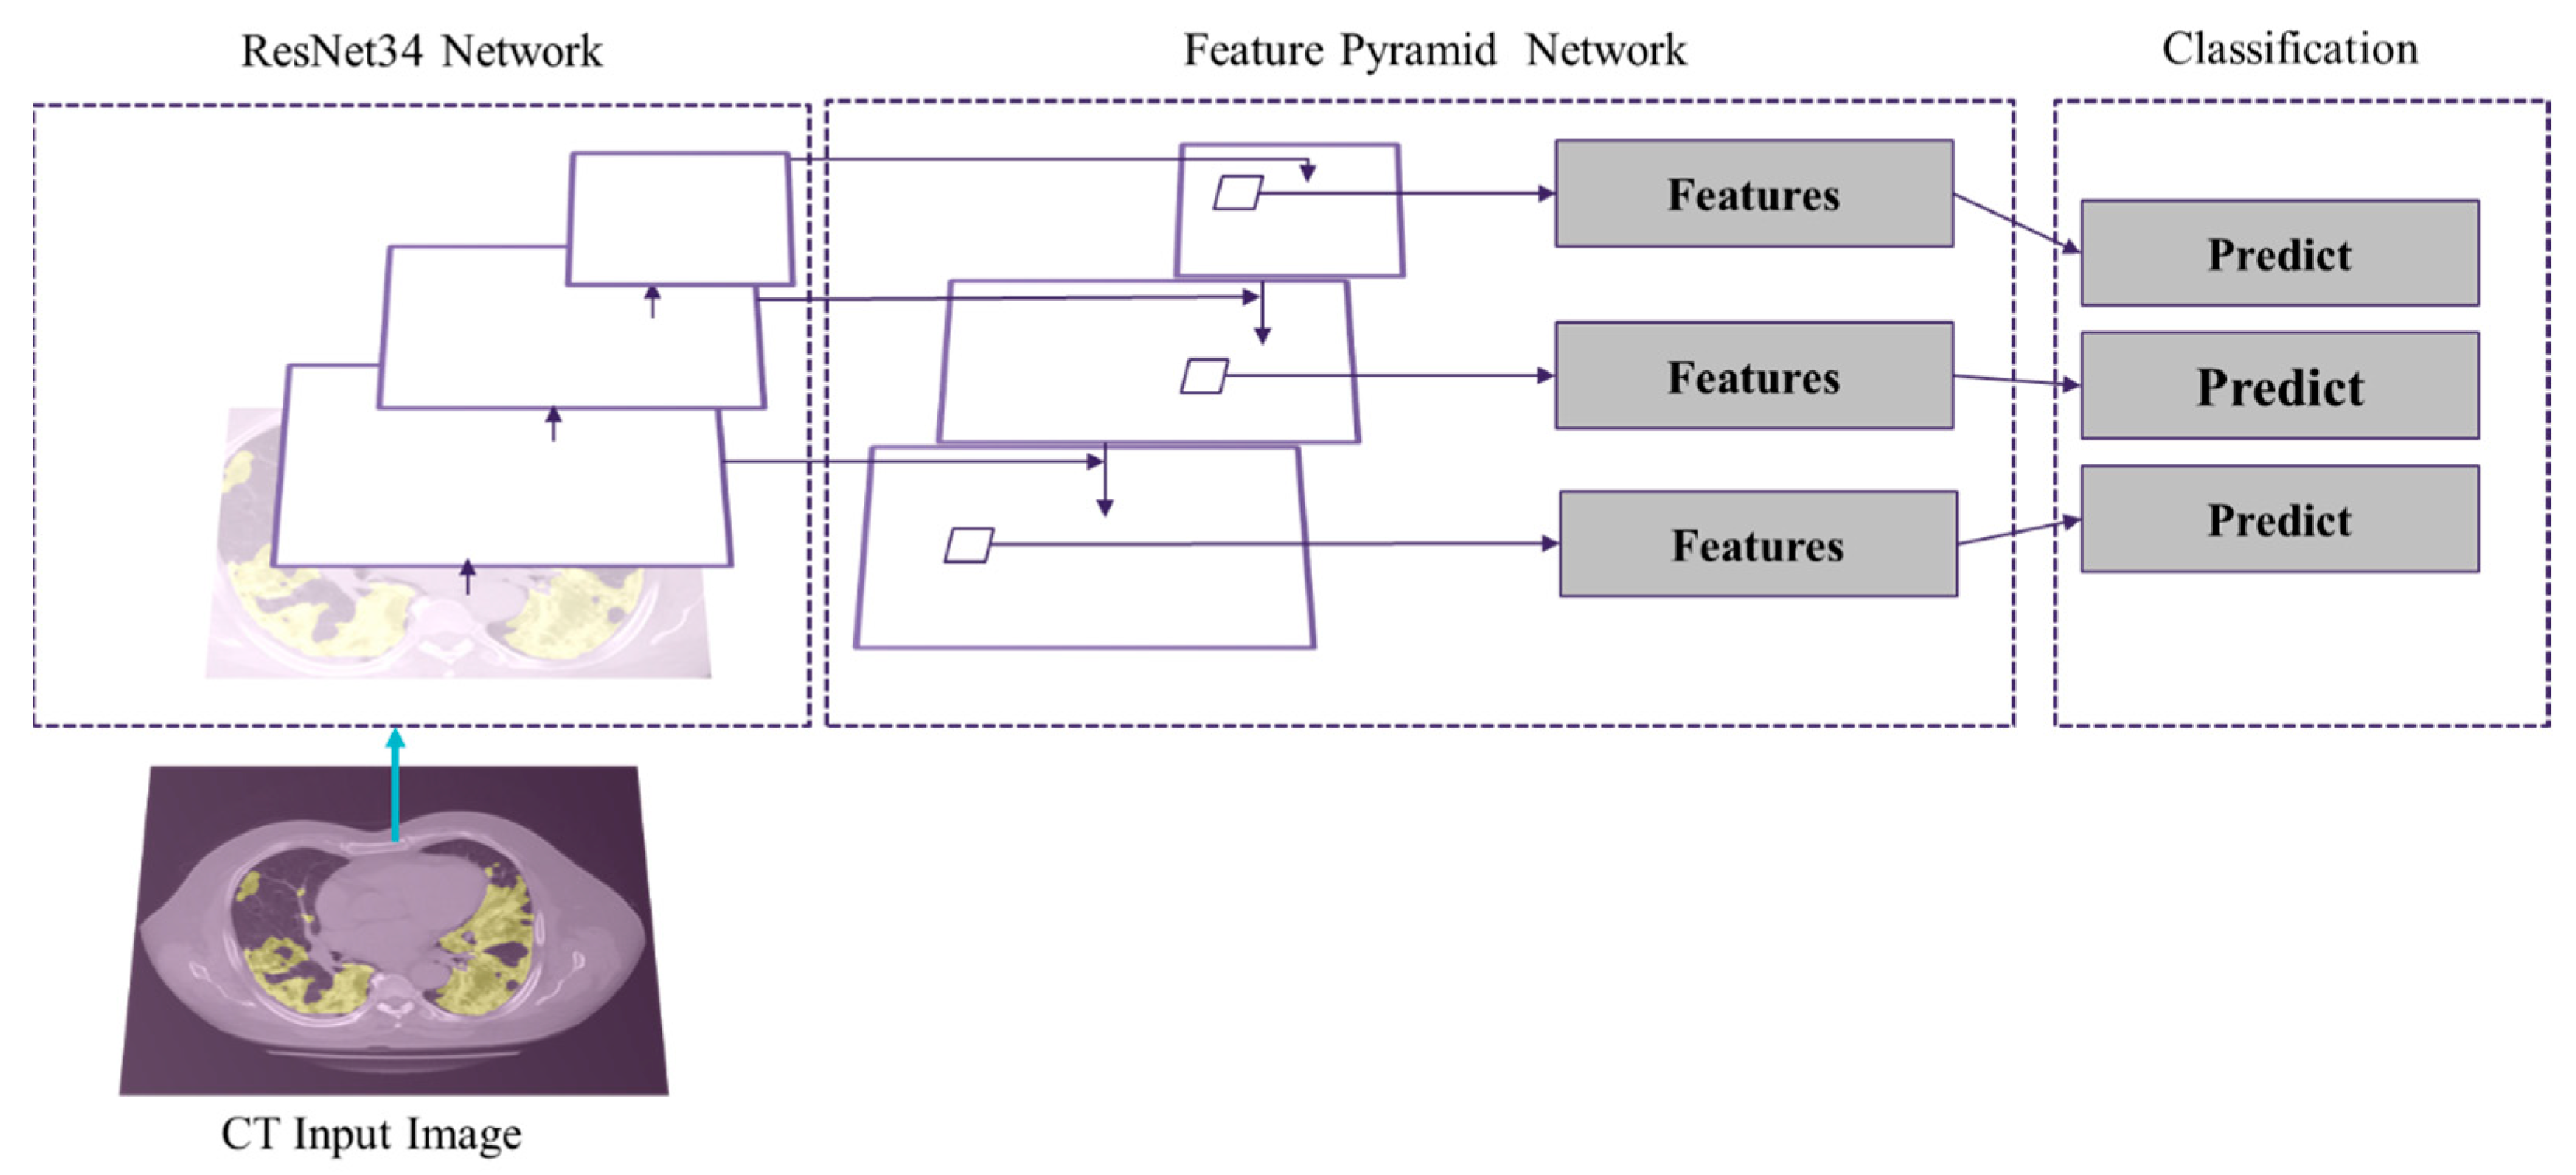

2.3.3. Segmentation of GGO and Consolidation Patches

2.3.4. Integrated Model and GUI